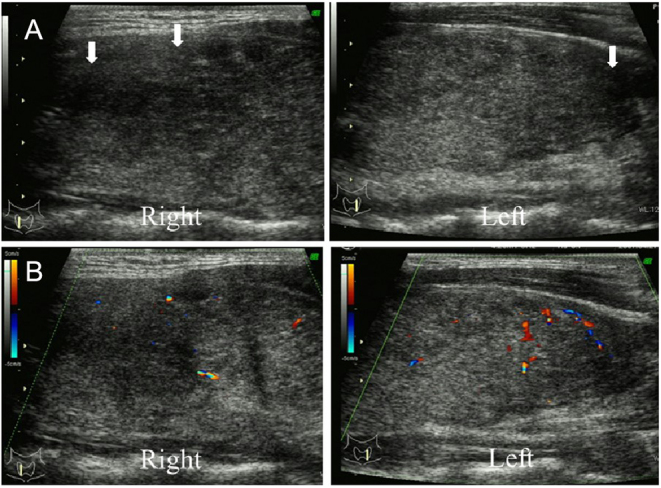

Methods and results: Seven patients diagnosed with SAT during pregnancy at our institution from January 2004 to December 2021 were identified, and their clinical findings were retrospectively examined. At SAT diagnosis, the median age was 34 (range: 31-42) years, the median duration of pregnancy was 5 (4-24) weeks, and all patients had neck pain but no fever. On laboratory examination, median (range) free thyroxine, free triiodothyronine, and C-reactive protein levels were 2.66 (1.14-7.77) ng/dL, 7.1 (3.3-16.1) pg/mL, and 2.22 (0.42-5.79) mg/dL, respectively, and all patients had a hypoechoic lesion of the thyroid gland. Three patients (43%) were treated with steroids, and three patients (43%) received replacement therapy with levothyroxine for hypothyroidism following destructive thyroiditis. There were no pregnancy complications in any of the cases. These seven patients (pregnancy group) were compared with 217 non-pregnant female patients (non-pregnancy group) aged 31 to 42 years who were diagnosed with SAT at our institution from 2016 to 2019. The frequency of body temperatures above 37°C was lower in the pregnancy group than in the non-pregnancy group (0% vs 65%).

目的:关于妊娠期亚急性甲状腺炎(SAT)的报道很少。本研究旨在阐明妊娠期亚急性甲状腺炎的临床特征:方法:研究人员对我院 2004 年 1 月至 2021 年 12 月期间确诊的 7 例妊娠期亚急性甲状腺炎患者的临床表现进行了回顾性研究。确诊 SAT 时,中位年龄为 34 [31-42]岁,中位孕期为 5 [4-24] 周,所有患者均有颈部疼痛,但无发热。实验室检查结果显示,游离甲状腺素、游离三碘甲状腺原氨酸和C反应蛋白水平的中位数(范围)分别为2.66(1.14-7.77)纳克/分升、7.1(3.3-16.1)皮克/毫升和2.22(0.42-5.79)毫克/分升,所有患者均有甲状腺低回声病变。3名患者(43%)接受了类固醇治疗,3名患者(43%)接受了左甲状腺素替代治疗,以治疗破坏性甲状腺炎引起的甲状腺功能减退症。所有病例均未出现妊娠并发症。这7名患者(妊娠组)与2016年至2019年在本院确诊为SAT的217名31至42岁非妊娠女性患者(非妊娠组)进行了比较。妊娠组患者体温超过37°C的频率低于非妊娠组(0%对65%):结论:与非妊娠期SAT患者相比,妊娠期SAT患者的发热可能较少。本研究中,妊娠组未出现妊娠并发症。这表明,通过对SAT(包括破坏性甲状腺炎后的甲状腺功能减退症)进行适当的治疗,可以避免不良的妊娠结局。